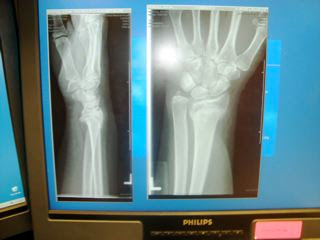

This is an x-ray of my well healed wrist. The technician took a buzz saw to my cast and off it came. It was scary and I felt an uncomfortable warmth when the blade neared the swollen part of my wrist. Afterwards I could wash my whole hand and arm. The fingers looked white, the tanned skin of my wrist and arm flaked off like on a glazed donut. That wrist still looks plump and feels very odd. I can’t hold a coffee cup even empty in my left hand. Actually, the doctor observed me holding my book in it and was impressed. But I did go swimming and soaking in the hot tub as therapy.